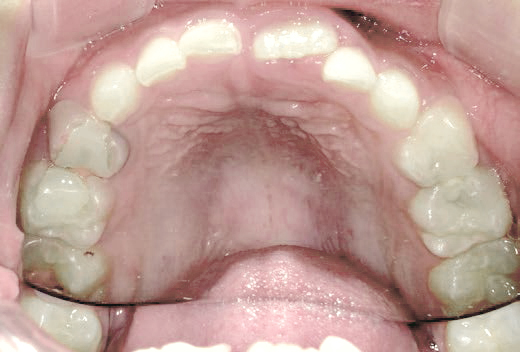

さらに、上からあごの骨を見たところ、中央がくびれた“ひょうたん型”に変形しており、あごの成長にも偏りが見られました。

診断の結果、前歯の中心も少し左にずれており、特に犬歯が生えるスペースが足りない状態でした。